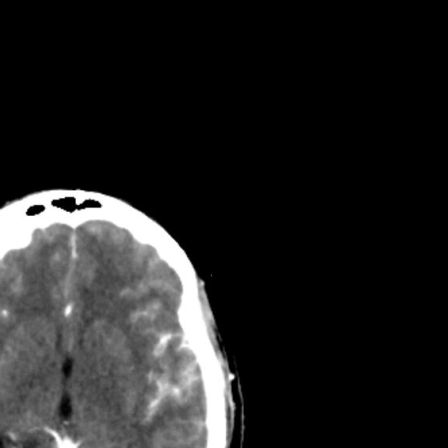

Brain non-contrast

Illustrations for clear understanding

Real scan images